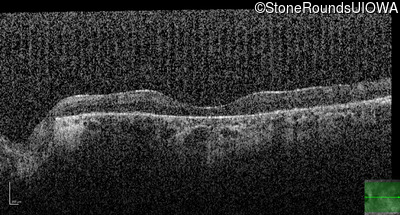

Optical Coherence Tomography - Left - 10/160 -2

Exemplar / OCT Stack